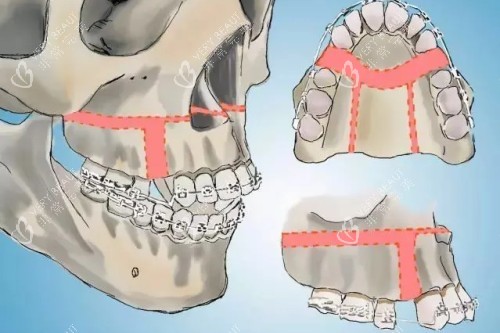

面诊那天,医生拿着我的CT片,指着骨头说:“你这是上颌前突+下颌后缩,得做双颌手术——上颌截骨后移,下颌截骨前移。”我听得云里雾里,只问了一句:“能让我侧脸不凸吗?”医生笑:“术后你的侧脸会立体很多,但得做好心理准备:前三个月肿得像猪头,半年才能正常吃饭。”我咬咬牙:“做!”

术后前三个月,我像“养伤正规户”——每天喝粥、吃蒸蛋,连苹果都得打成泥。第四个月开始,能嚼软饭了,但硬的东西还是不敢碰。第六个月复查时,医生拿着我的对比照说:“侧脸变化非常大,上颌收了5毫米,下颌前移了3毫米,现在比例很协调。”